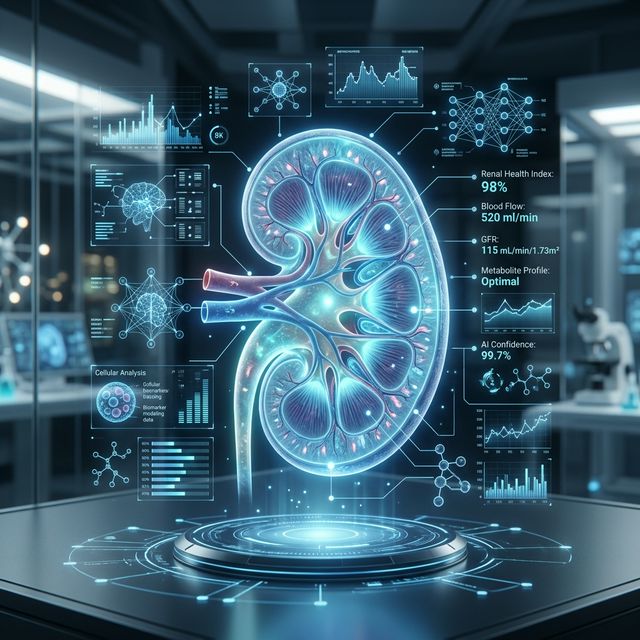

O diagnóstico precoce e a IA tornam-se essenciais para a saúde dos rins em 2026.